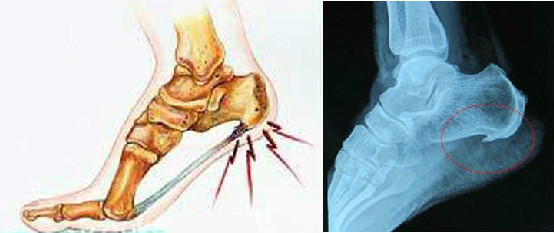

足底筋膜炎:只值夏日,很多女生会选择穿着平底凉鞋出门,此类鞋子的鞋底平坦,没有对足部关键部位起到支撑作用,加之材质坚硬,极其容易出现足底筋膜炎。

崴脚:女生的通病,在平地上行走都有可能出现崴脚、跌倒的现象,这与Q角度过大有着密不可分的关系。

骨刺:爱美的女性经常会穿着高跟鞋,由于高跟鞋的受力面积很小,人的后跟将承受更大的压力,久而久之容易形成骨刺。